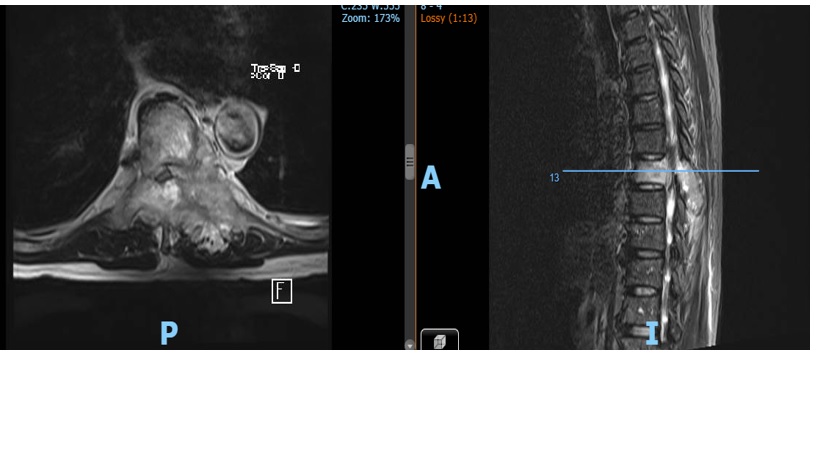

MRI cột sống ngực

Kết quả MRI cột sống ngực có gadolium:

Thâm nhiễm tủy xương đốt sống ngực T8 lan ra mô mềm xung quanh và vào ống sống chèn ép tủy

Chẩn đoán xác định: chèn ép tủy sống ngực T8